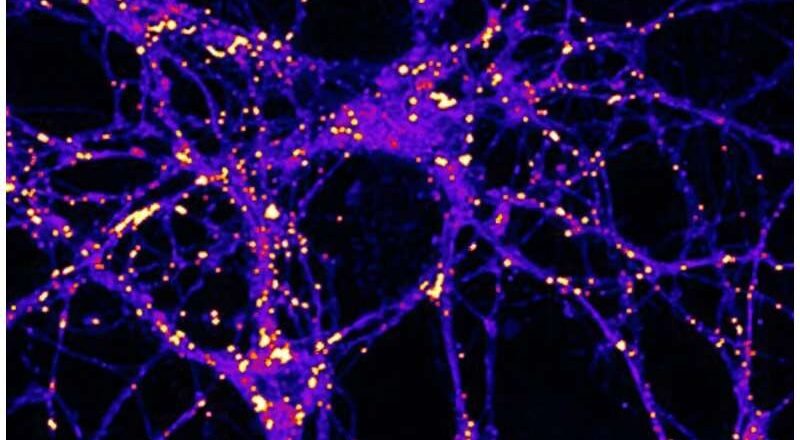

Las neuronas queman el azúcar de forma diferente: un descubrimiento ofrece una nueva esperanza para combatir la neurodegeneración

Un nuevo estudio realizado por científicos del Instituto Buck para la Investigación del Envejecimiento ha revelado un factor sorprendente en la lucha contra el Alzheimer y otras formas de demencia: el metabolismo cerebral del azúcar. Publicado en Nature Metabolism , la investigación revela cómo la descomposición del glucógeno (una forma almacenada de glucosa) en las neuronas puede proteger al cerebro de la acumulación de proteínas tóxicas y la degeneración.

El glucógeno se considera generalmente una fuente de energía de reserva almacenada en el hígado y los músculos. Si bien también existen pequeñas cantidades en el cerebro, en particular en las células de sostén llamadas astrocitos, su papel en las neur...